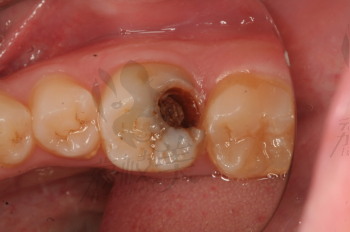

摘要:面對牙齒疼痛,特別是牙爛大窟窿帶來的困擾,需及時采取應對措施。建議盡快就醫(yī),進行專業(yè)牙齒檢查和治療。日常護理方面,注意口腔衛(wèi)生,定期刷牙,使用牙線和漱口水清潔口腔。飲食避免過冷過熱刺激,減少糖分攝入,以防細菌滋生。如需緩解暫時疼痛,可服用止痛藥,但不可長期依賴。預防牙爛,定期口腔檢查至關重要。

牙齒疼痛是常見的口腔問題之一,而牙爛了個大窟窿晚上痛更是讓人難以忍受,這種情況不僅影響生活質(zhì)量,還可能引發(fā)其他口腔疾病,本文將為您解析牙爛窟窿的原因,并探討應對方法和預防措施。

1、齲齒:齲齒是牙齒爛掉的主要原因之一,長期不注意口腔衛(wèi)生,細菌滋生導致牙齒逐漸腐蝕。